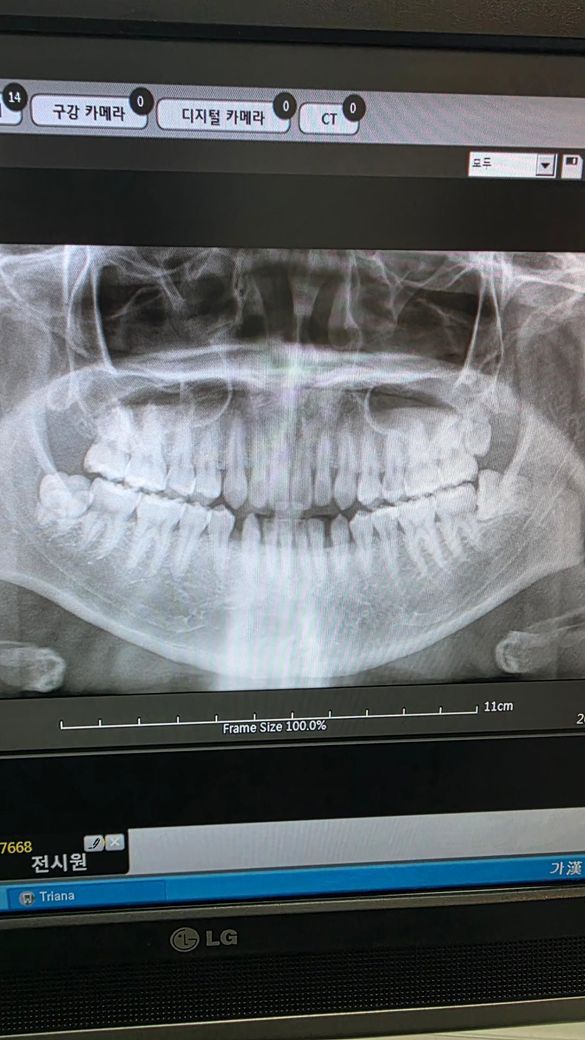

위에쪽 소구치가 신경치료를 해야할정도로 심하다는데 평생 통증도 없었고 아픈쪽은 아래쪽 사랑니쪽 치아인데 갑자기 통증도없는 위쪽을 신경치료하자해서 일단 검진만 받고 나왔는데 진짜 충치가 많이 심한가요? 보는법을 모르겠네요

• 2번 째 사진

치근단사진(작은 사진)에서 위 작은어금니의 치근단에 약한 염증 반응이 보이고, 충치로 의심되는 인접면 부위 양상이 있긴 합니다 다만, 좀 더 명확히 보려면 다른 각도로도 찍어보고 여러 임상테스트도 해봐야 할 것 같습니다

증상 없이도 신경치료를 해야할 정도의 충치인 경우는 있을수 있습니다